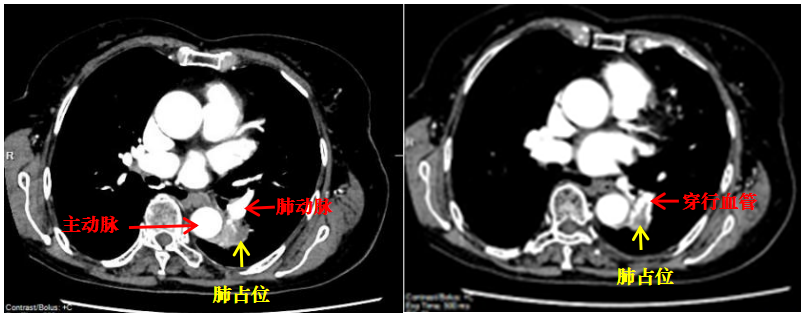

患者胸部增强CT

该患者为老年女性,因“反复咳、痰、喘10余年,再发加重10余天”入院,既往有高血压、糖尿病病史,肺功能较差。入院后胸部增强CT显示,其左肺下叶有一大小约2.7×2.0cm的不规则实性结节,增强后不均匀强化,内有肺动脉穿行,Lung-RADS 4X类,恶性可能性极高。常规电子支气管镜检查未能找到恶性肿瘤细胞,而患者及家属因老人高龄、基础病多,拒绝接受外科活检及手术。

经MDT多学科会诊,专家组建议实施CT引导下肺组织穿刺活检,为后续精准治疗提供依据。但该结节周围毗邻胸主动脉和肺动脉,穿刺位置稍有偏离就可能引发大出血,危及患者生命,手术难度与出血风险极高。